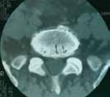

Poročilo o primeru: Diagnostični postopki so sprva razkrili le intraspinalni razlog za bolečino. Vsi trije bolniki so bili operirani, vendar kliničnega izboljšanja po operaciji ni bilo. Dodatni diagnostični postopki, pri enem od bolnikov pa obdukcija, so kot razlog za vztrajajočo bolečino pri dveh bolnikih razkrili tumor živčnih ovojnic, pri tretjem bolniku pa medenični absces s kompresijo lumbosakralnega pleksusa.